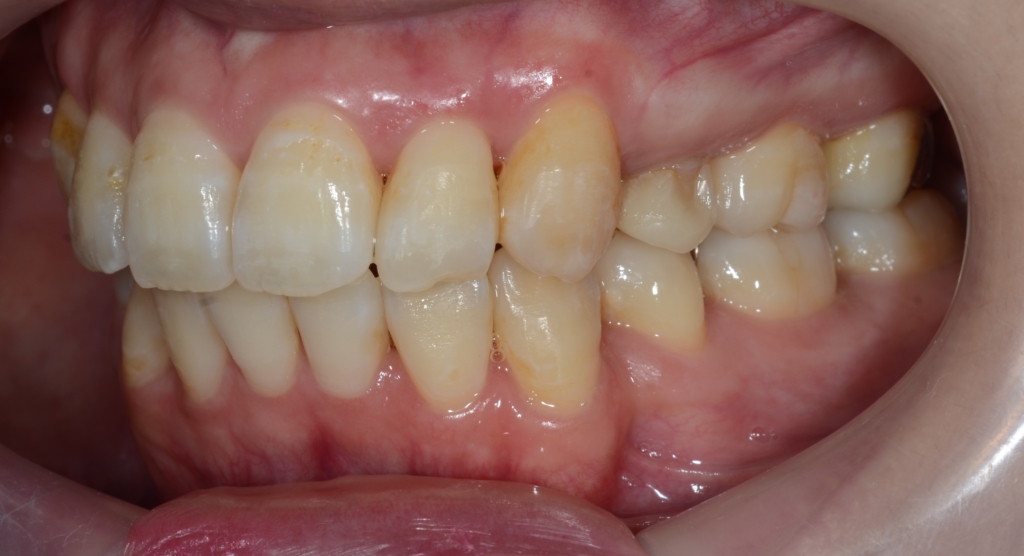

患者さんは、30代の女性(社会人)です。

「八重歯などのガタガタを治してきれいな歯並びになりたい!」

というのが一番の希望でした。

合わせて、口元が少しでも引っ込んで、お口を閉じる時にオトガイ辺りの「力」が抜けてしわが無くなればもっと嬉しい!とのことでした。

【Before】

#1.顎と歯の不調和による叢生(重度)

#2.上顎前突(出っ歯)傾向

と診断しました。